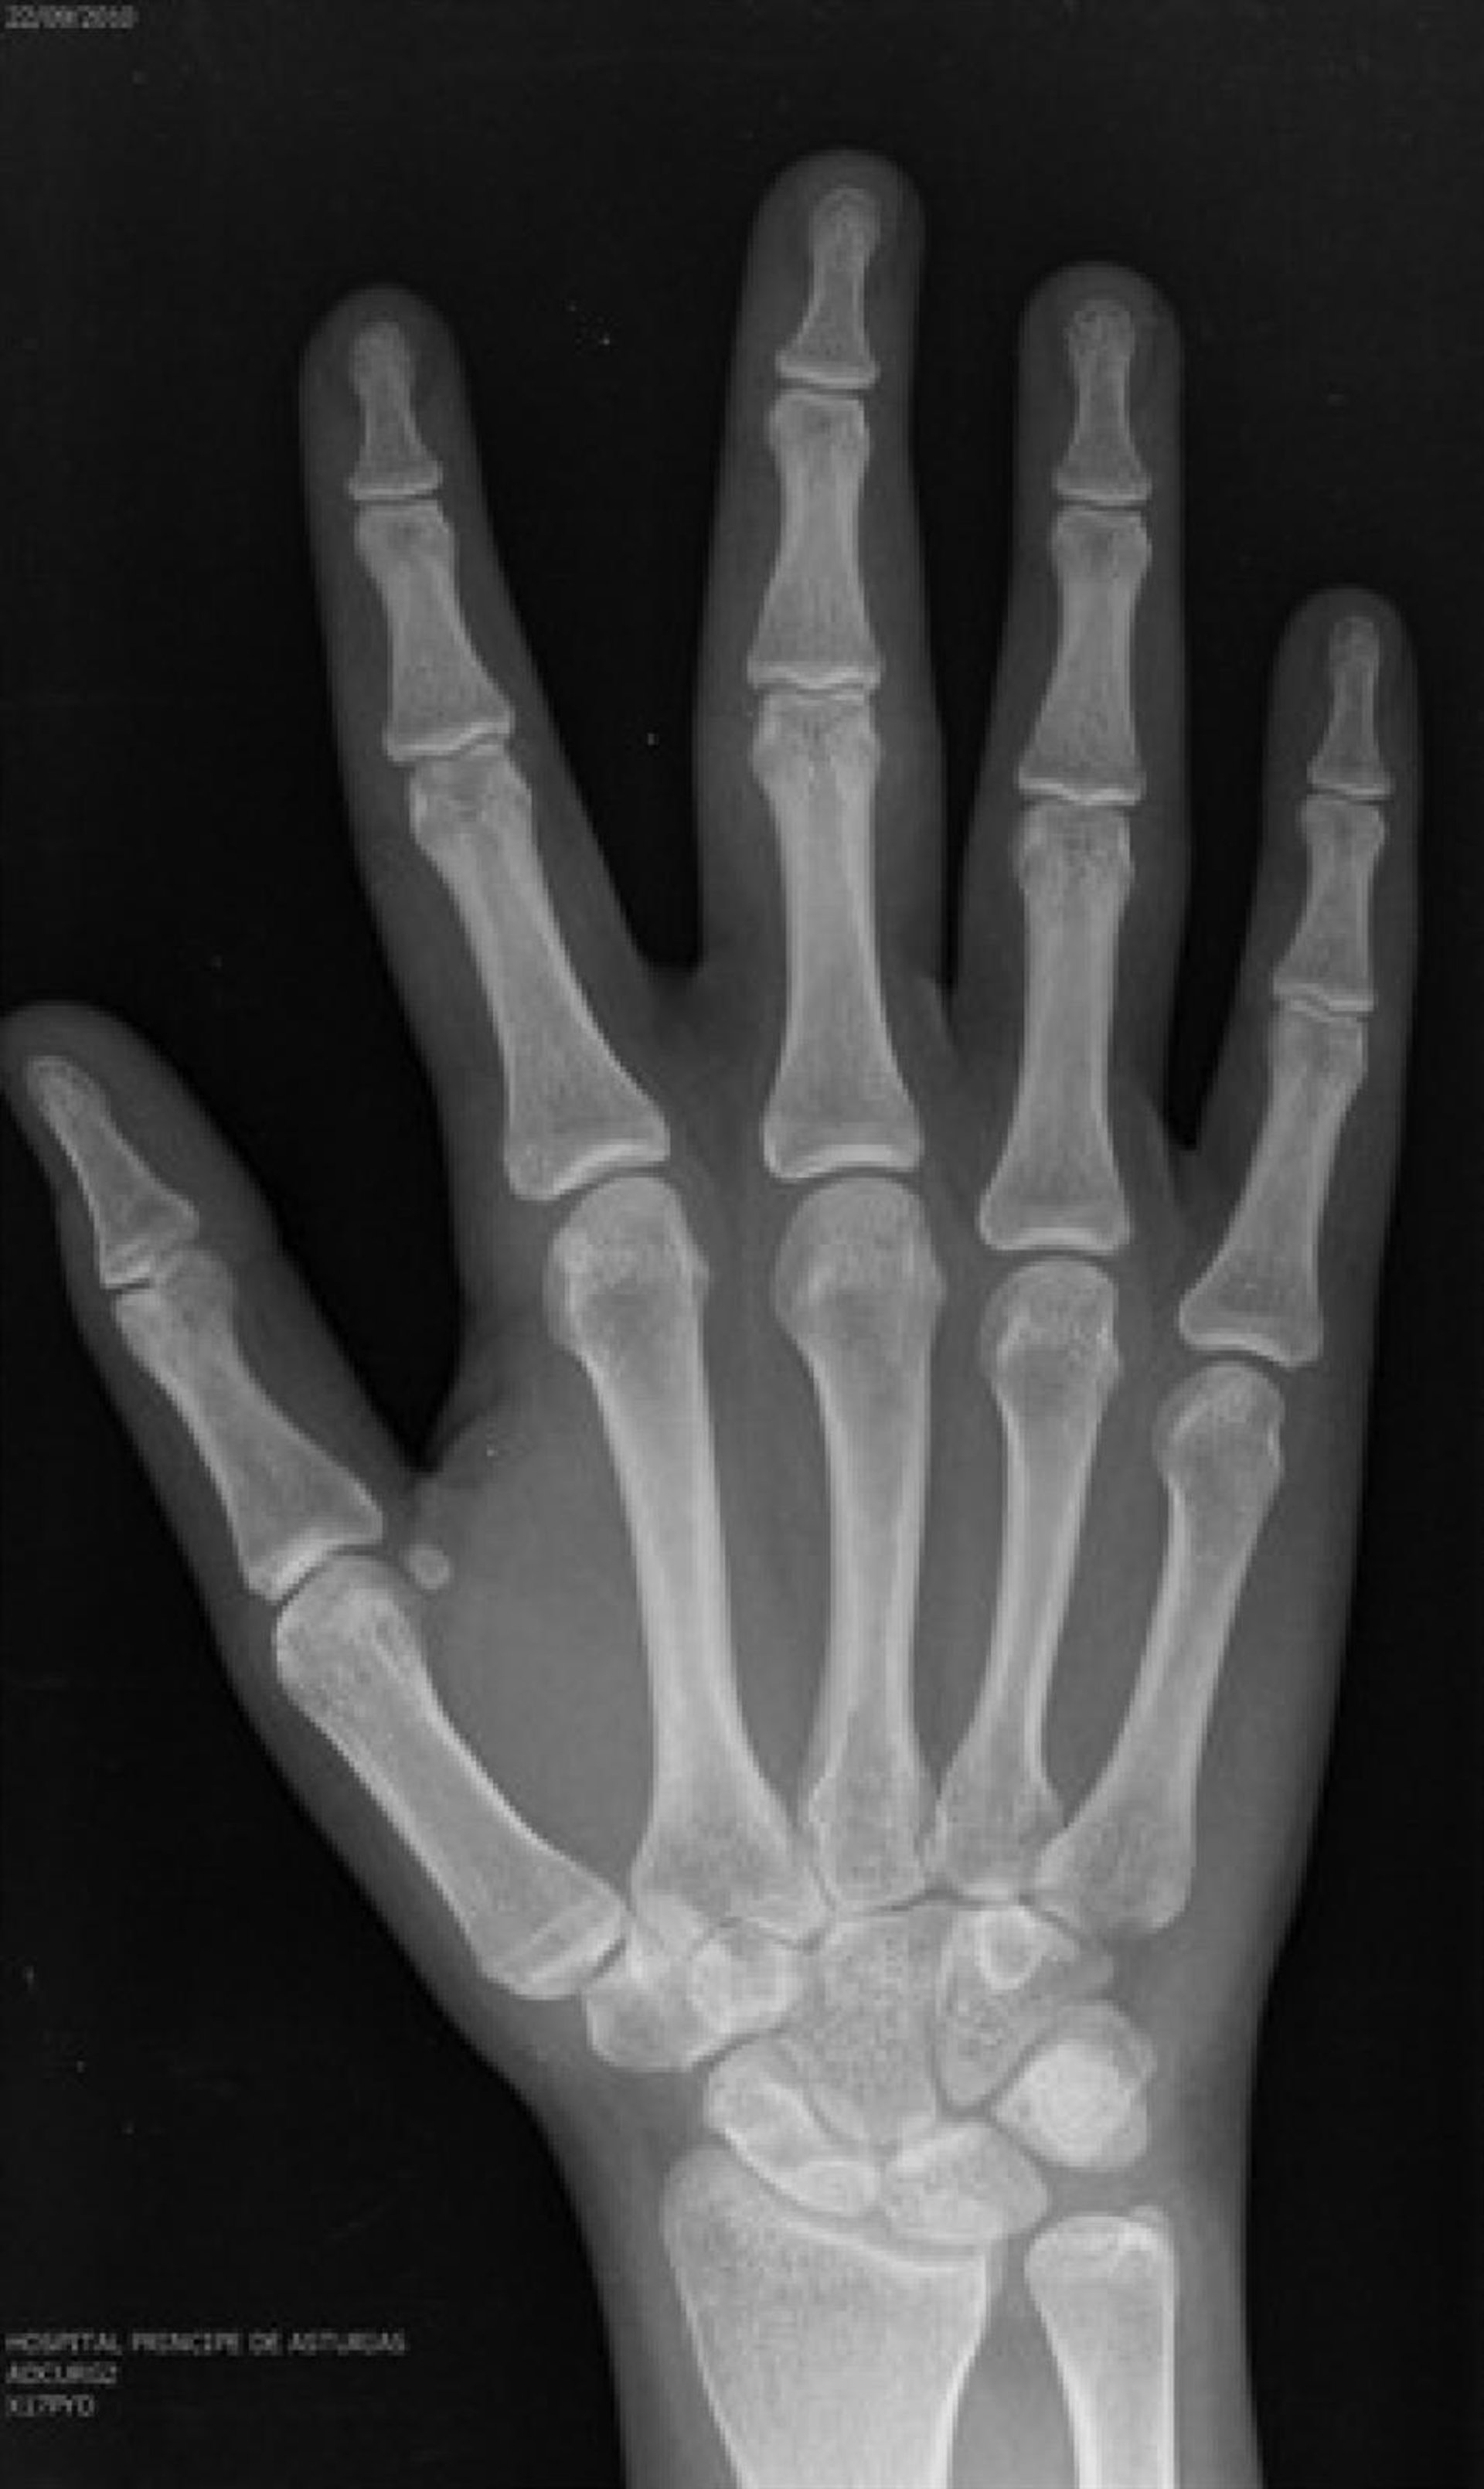

En la actualidad, la práctica más extendida es una radiografía de la muñeca, con la que el radiólogo deduce la edad del sujeto, sin necesidad de verle, aplicando unas tablas estadísticas de crecimiento elaboradas en los años cincuenta en Estados Unidos sobre varones de raza blanca. El resultado "nunca es exacto" y arroja una horquilla que puede llegar a ser de más de tres años, de modo que un joven de 16 puede ser tomado por un adulto de 19. Por eso, Cava de Llano ha reclamado que todas las pruebas sean interpretadas por un especialista que, además, examine al joven personalmente.